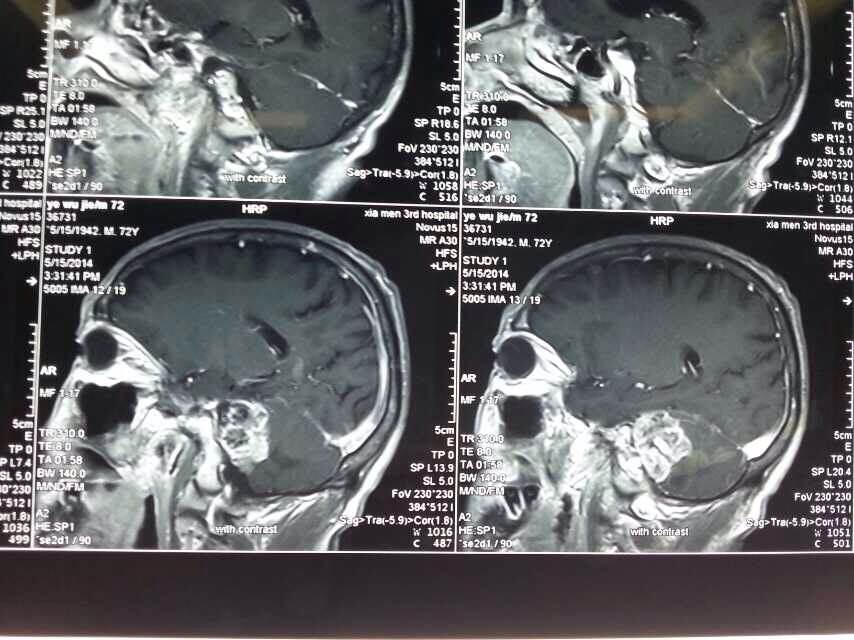

2014520是个特别的日子,第三医院手术室灯火通明,神经外科调集所有的技术团队手术一台接一台,有脑动脉瘤破裂的,有脑外伤出血的,忙碌不停。